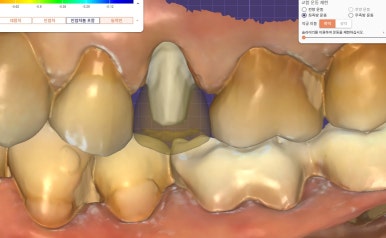

파절된 보철을 제거한 뒤,

치아 상태를 정밀하게 체크했습니다.

![]() |

✅ 다행히 치아 뿌리와 구조 모두 건강했고,

✅ 신경치료나 추가 보강 없이 바로 재보철이 가능했어요.